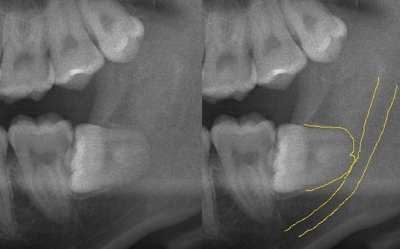

実際のレントゲン写真とCT画像を見てみましょう。

レントゲン撮影では明らかに

神経と歯根が重なって見えます。

今までではこの時点で病院口腔外科へ紹介でした。

でもCTを撮影すると、左下の画像みると

距離があるのがわかりますよね。

この方は、CT導入前に一度は紹介しようとしたのですが、仕事を休むことができず、消毒を繰り返してずっと様子をみていました。 今回距離がリスクが低いことがわかり当院で抜歯いたしました。 仕事休む必要がなかったため、非常に喜んでいただきました。